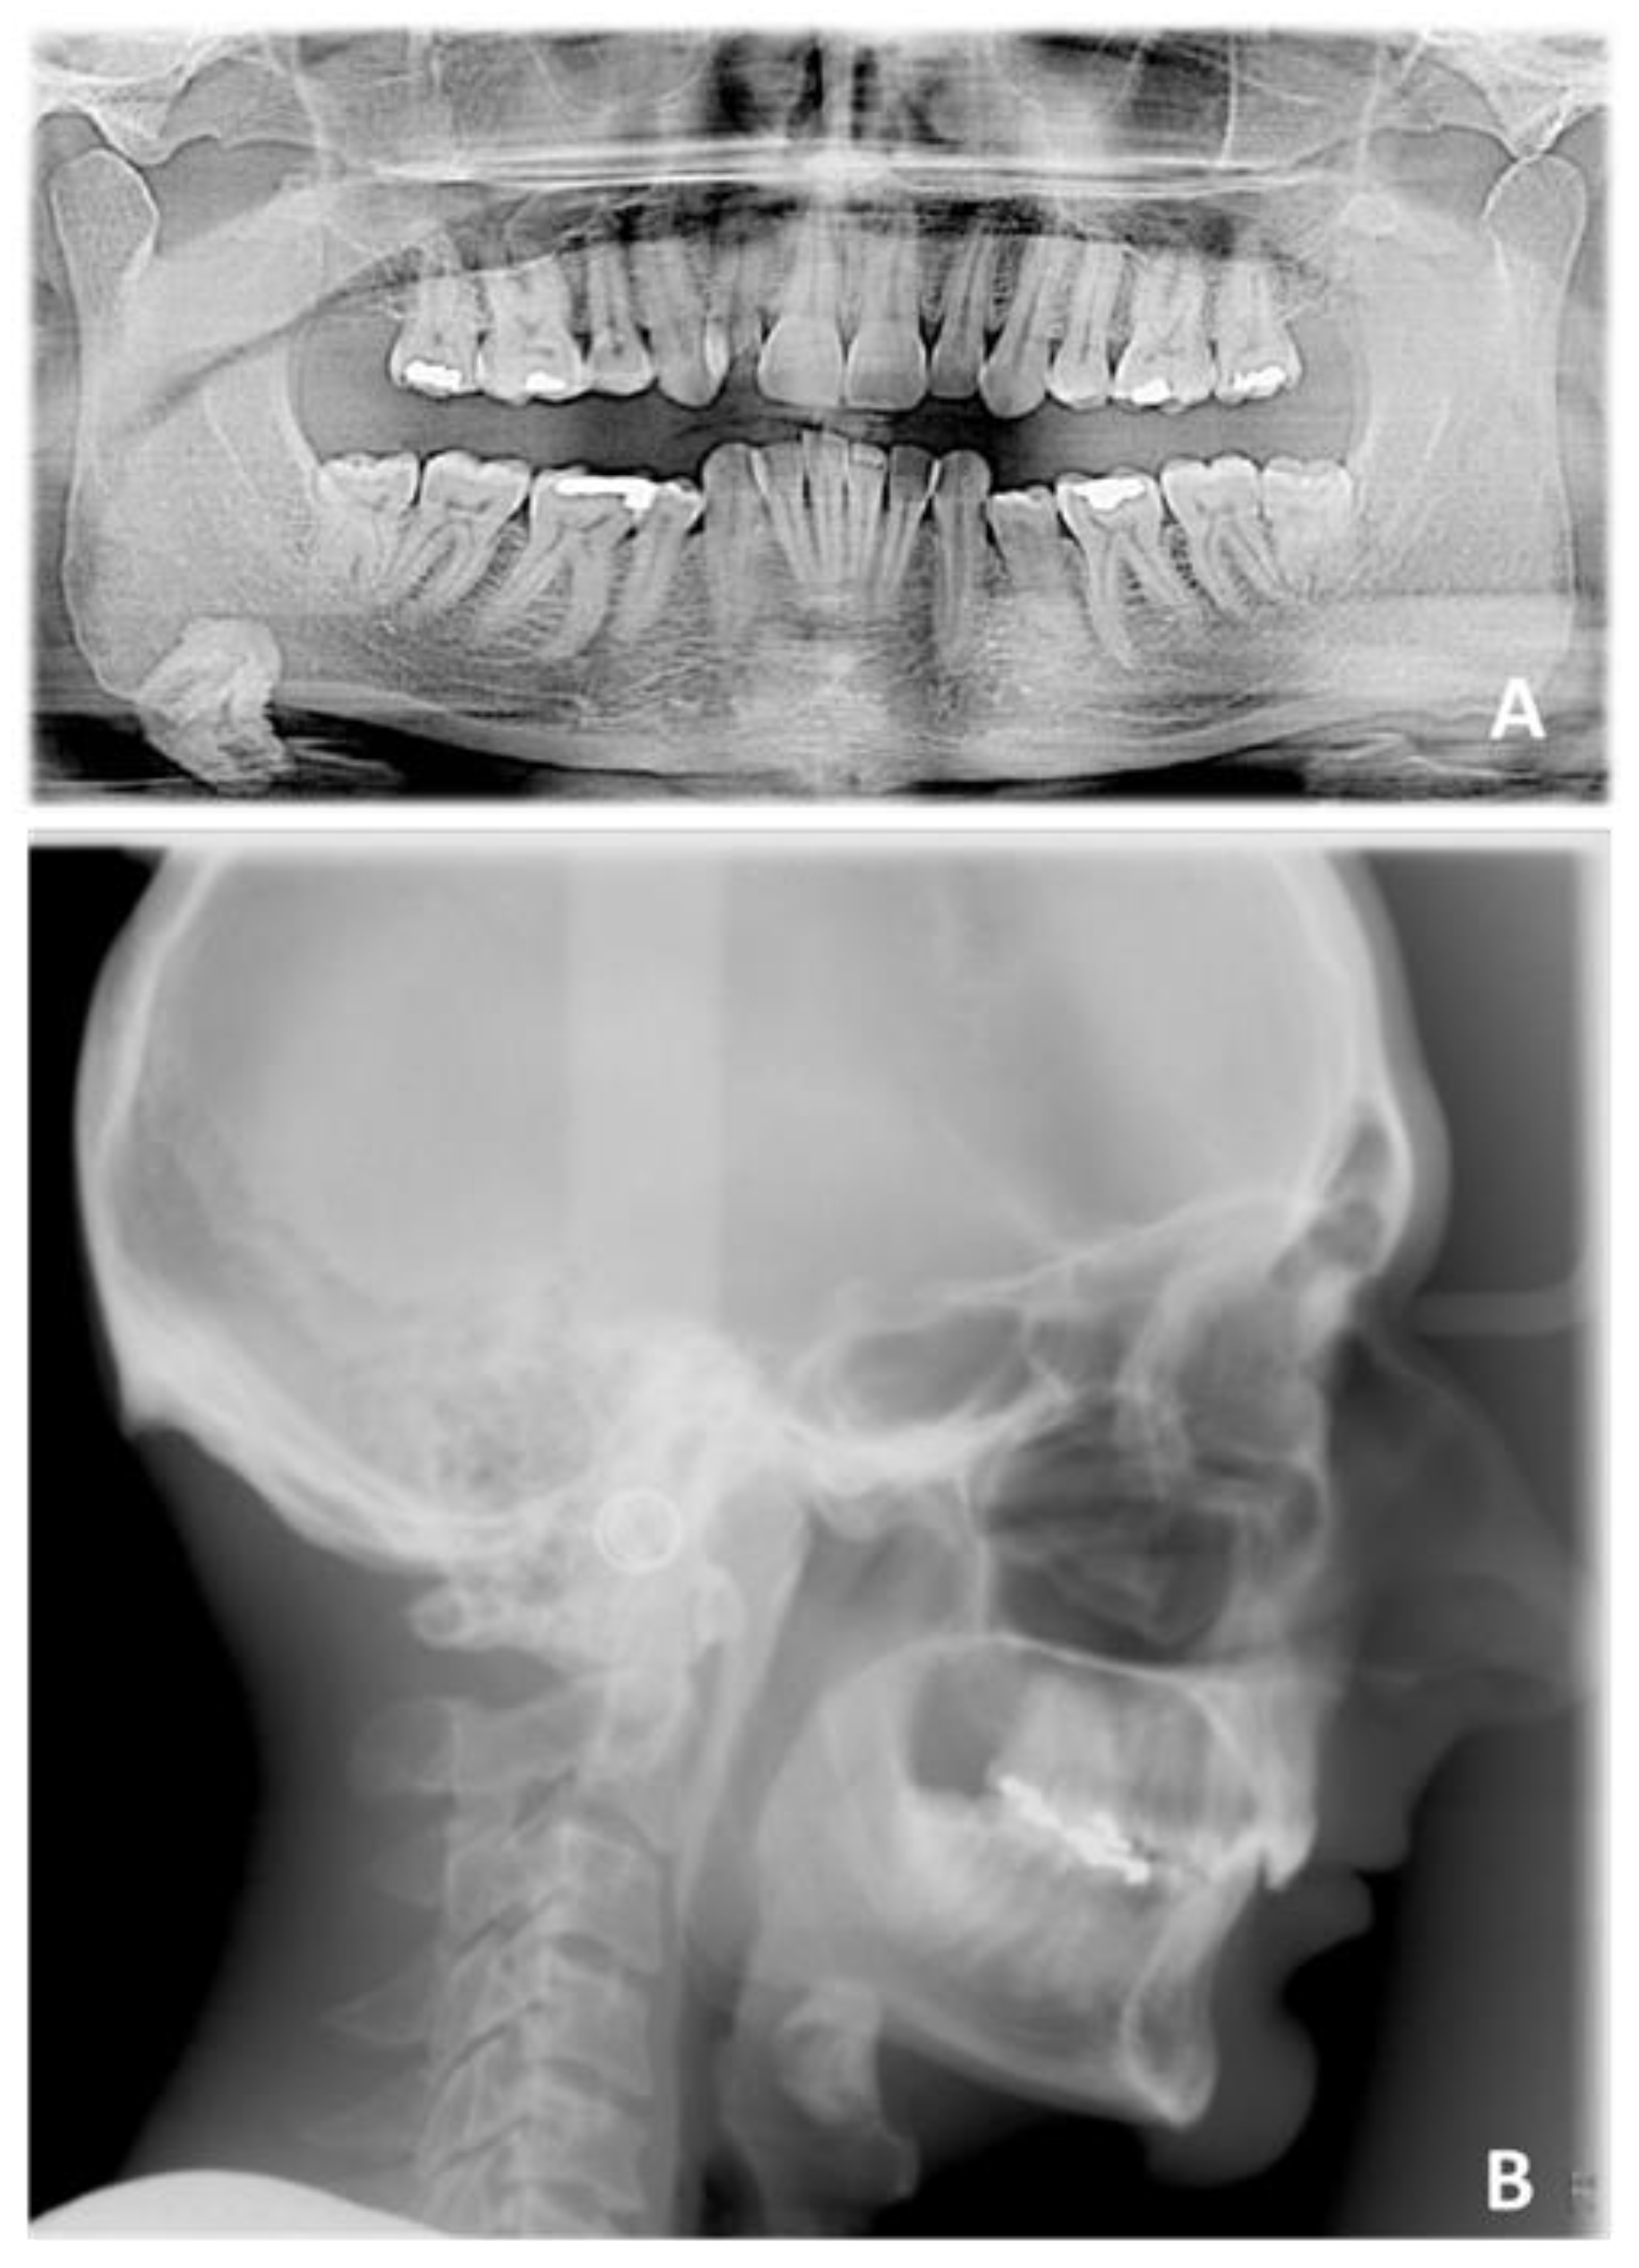

The second case was concerned with the orthodontic treatment with transparent aligners of a growing patient with dentoskeletal class II malocclusion, scissor bite of the first right upper premolar, a slight contraction of the upper and lower arches, lower dental crowding and an interincisive diastema.

The patient also had good exposure to their smile and deep bite, so it was indicated to correct the deep bite by leveling the lower arch with the intrusion of the canines and incisors (Figure 15 and Figure 16).

The patient presented a skeletal class II malocclusion, a normodivergent growth pattern, excessive proclination of the upper incisors and a normoinclination of the lower incisors (Figure 17 and Table 3).

Figure 16. Pre-treatment radiographic of case number 2: (A) orthopantomography; (B) lateral cephalogram.